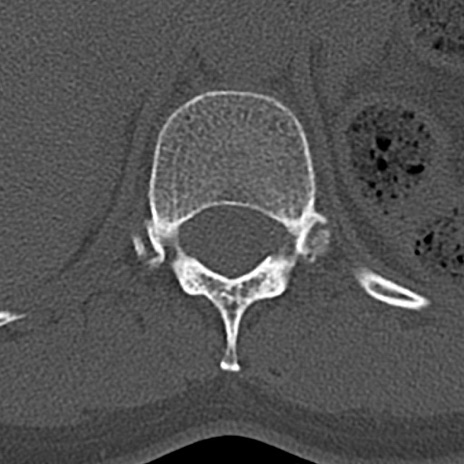

腰椎CT

横断像と矢状断像